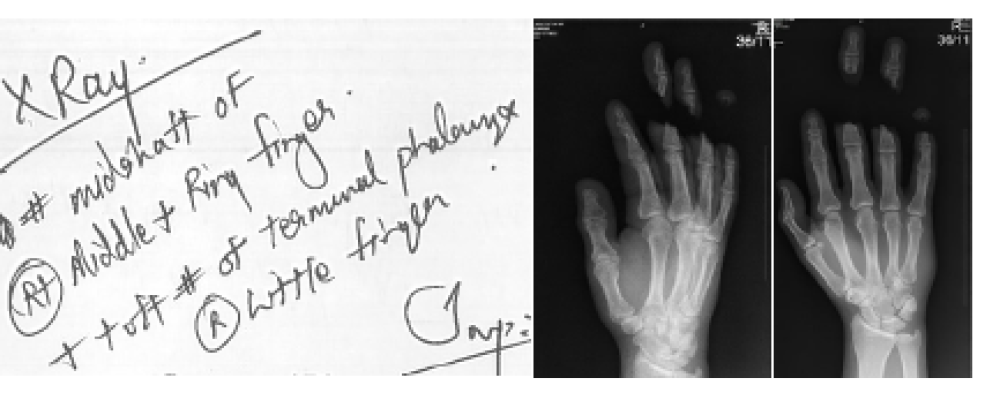

Brutal NHS Medical Negligence Leads to Amputation of Young Athlete’s Arm – Our Panel of Lawyers Secures £730,000 Compensation in Adam’s Case